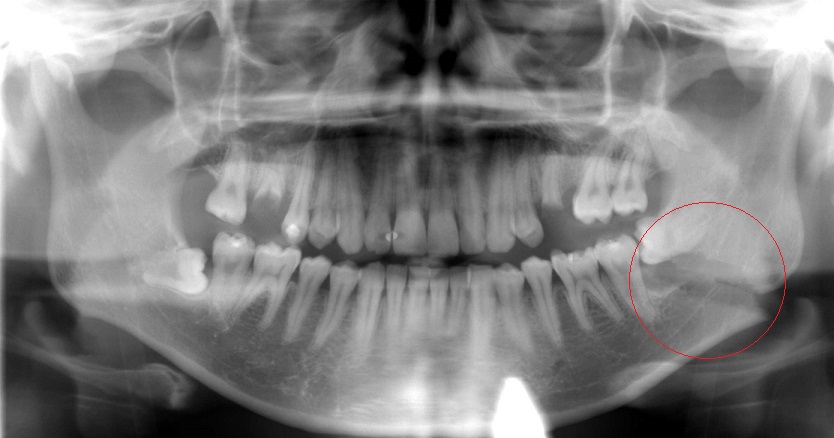

今日の抜歯(レントゲン付き)

今日は右下8の抜歯を希望されて来院された患者様の抜歯を行いました。手術時間は10分でした。患者さん曰く大学病院に紹介されたけど予約が取れずにいたところ当院をネットで見つけたそうです。 初診時に説明をおこないその場で抜歯を […]